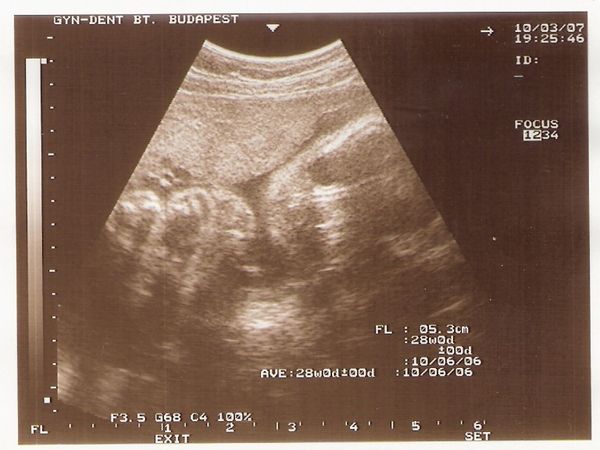

Születési dátumra nekünk a júni 28 „van kinézve”

Ugyanis akkor van a házassági évfordulónk, Máté baba akkor már több, mint 38 hetes lesz, és én ezt így kitaláltam, hogy az milyen szép is lenne! Akkor leszünk két éves házasok! Dodó most olvasom, hogy Nektek is esélyes a házassági évforduló! Drukkolok, hogy így legyen!